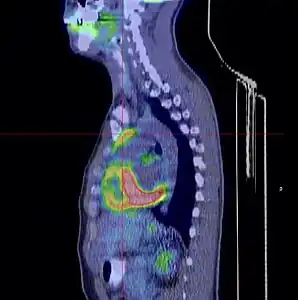

- Thymome de type B1 en TEP scanner

Coupe transversale. Les trois clichés sont extraits du même examen.

Coupe sagittale ; la tumeur est à l'intersection des lignes rouges.